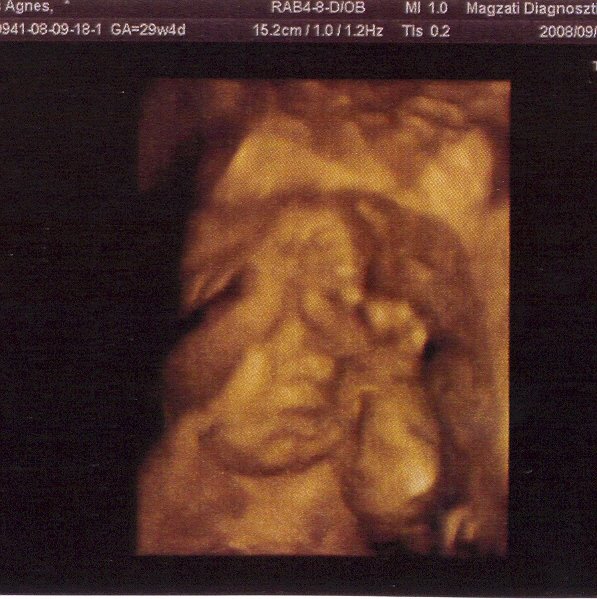

Most gyorsan egy kép a piciről. Csütörtökön voltunk UH-n és megint nagyon szégyenlősnek mutatkozott, mindig a kis arca elé tette a kezecskéit. Ez a kép mondható a legjobbnak. A minősége viszont lehetne jobb is, de csak így tudom berakni ide, még így is örülök, hogy egyáltalán sikerült.

Amúgy minden rendben velünk. Szépen fejlődik, a paraméterei nagyon jók, és sokát ficánkol. Kicsit furcsa, hogy még több mint 2 hónapom van, mert már annyira itt van velünk a kis pocaklakó. Évi is állandóan simogatja a hasamat és beszél a kicsiről és persze mi is. Nekem egyébként még mindig hihetetlen egy kicsit, úgyhogy reggel mindig megtapogatom gyorsan és megnézem a tükörben a pocimat. :lol: Jó látni, hogy szép gömbölyű! Majd megpróbálok megint képet feltenni róla.

Kép